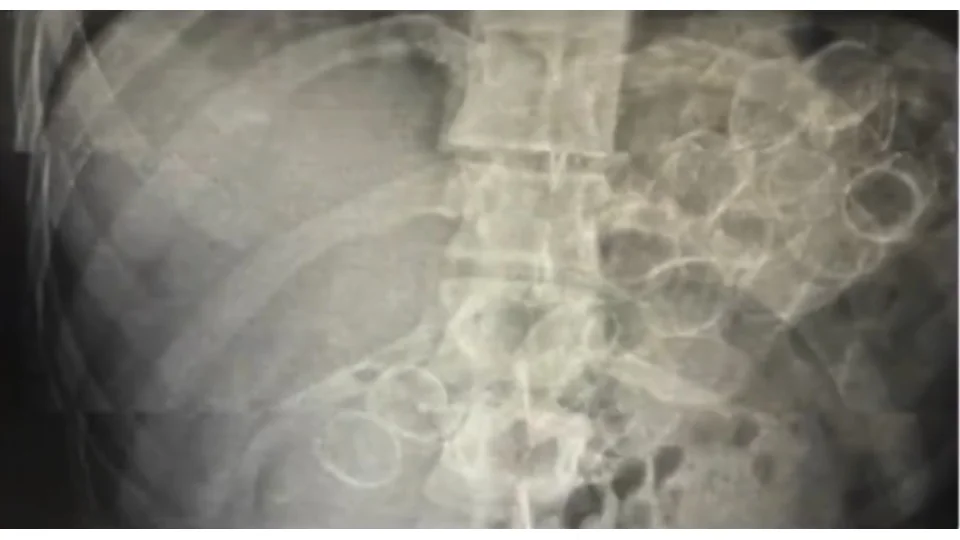

Bingöl'de polis ekiplerinin yaptığı çalışmada mide ve bağırsaklarında 75 kapsül halinde 775 gram metamfetamin maddesi ele geçirilen 3 şüpheli tutuklandı

Bingöl'de polis ekiplerinin yaptığı çalışmada mide ve bağırsaklarında 75 kapsül halinde 775 gram metamfetamin maddesi ele geçirilen 3 şüpheli tutuklandı.

Bingöl İl Emniyet Müdürlüğü Narkotik Suçlarla Mücadele Şube Müdürlüğü ekiplerince yürütülen çalışmalar neticesinde, "Uyuşturucu veya Uyarıcı Madde Ticareti" suçu kapsamında 3 şahsın "yutma ve tıkma" yöntemiyle mide ve bağırsaklarında yüklü miktarda uyuşturucu madde taşıyarak kente getirdiği belirlendi.

Ekipler tarafından yakalanan şüphelilerin hastanede yapılan tedavileri sonucunda, toplam 75 kapsül halinde 775 gram metamfetamin maddesi ele geçirildi.

Gözaltına alınan 3 şüpheli, emniyetteki işlemlerinin ardından sevk edildikleri adli makamlarca tutuklanarak cezaevine gönderildi.